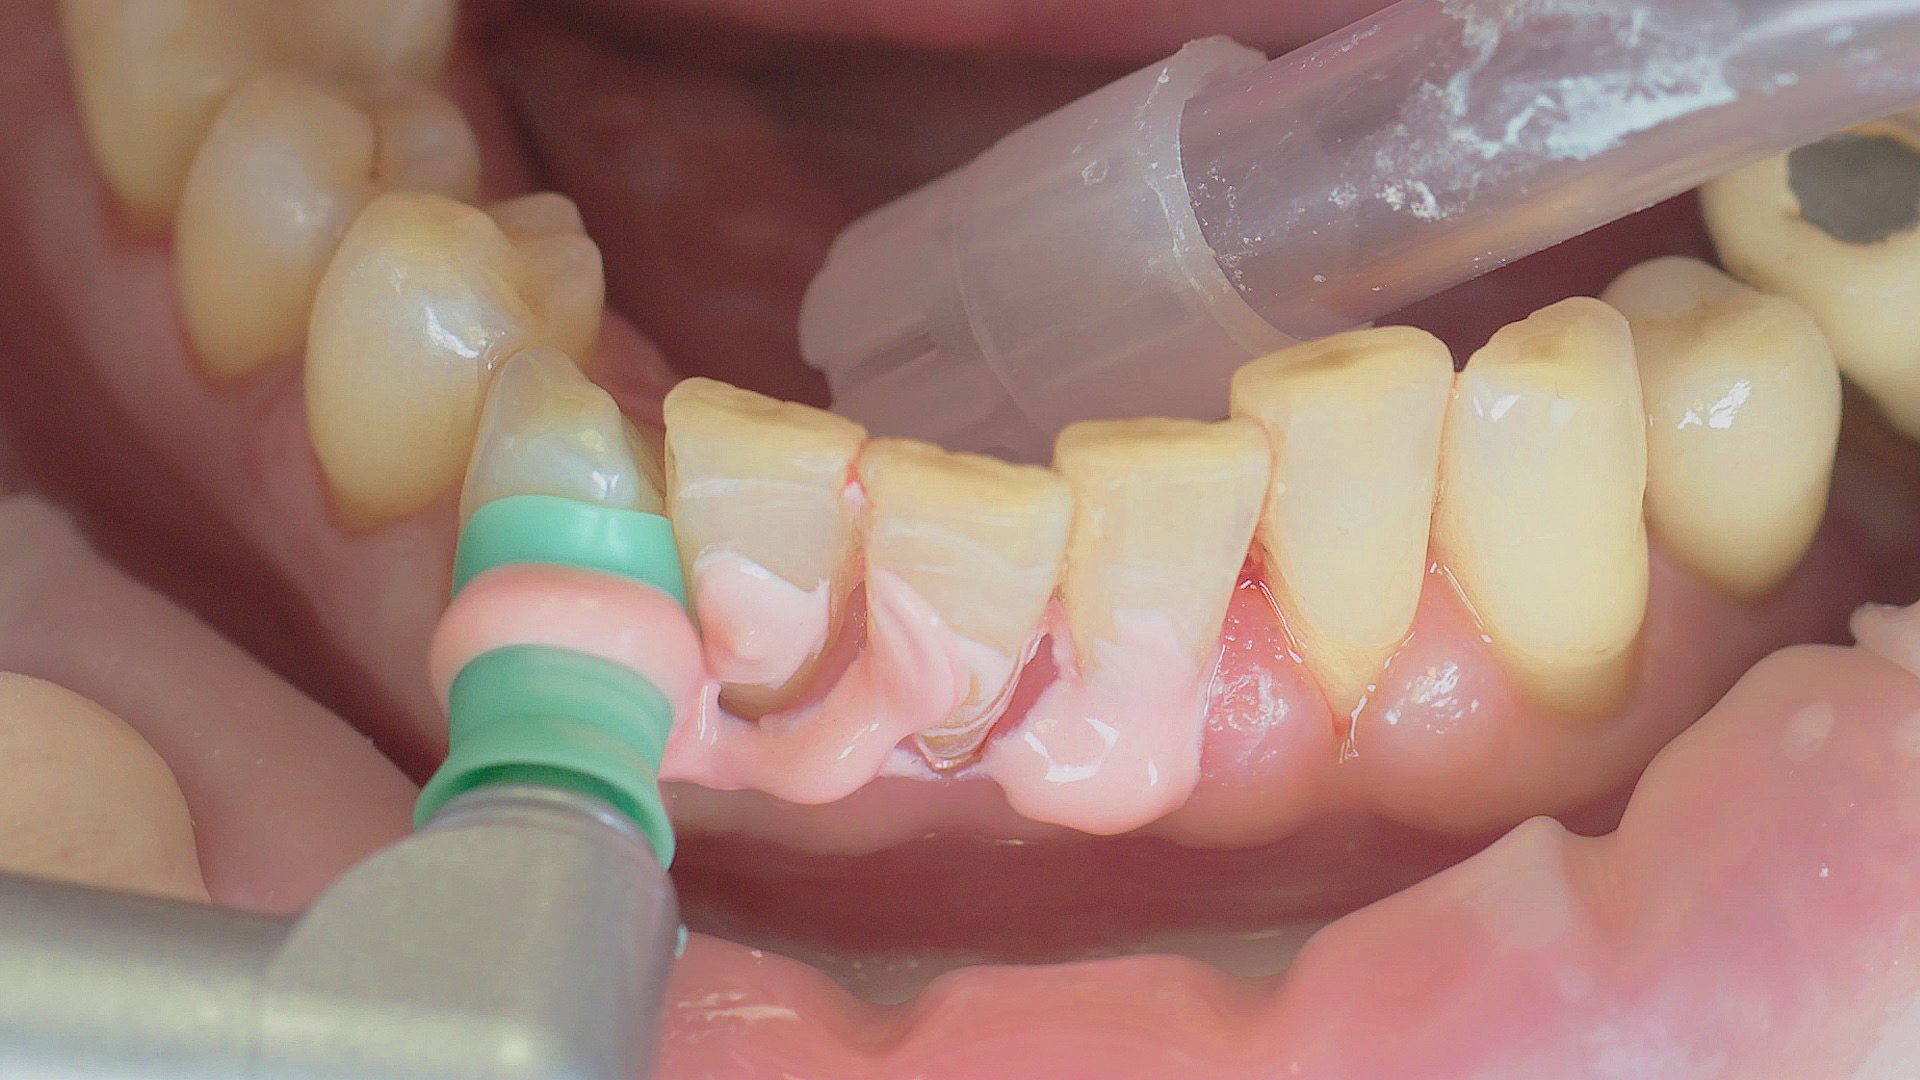

Every dental examination is based on a detailed medical history combined with targeted diagnostics con- taining as much detail as possible: The dentist records systemic risk factors such as diabetes or smoking and identifies any potential increased tendency to inflammation.[3] Hard and soft tissues are examined and periodontal pockets are probed in a screening test according to PSR (Periodontal Screening and Recording). In case of abnormal findings, the periodontal status is then re- corded and therapy is initiated where necessary. This treatment begins with professional biofilm management, by using, for example, rotary cups and polishing com pounds (Fig. 1), and comprehensive instructions in oral hygiene. Sonic or ultrasonic systems remain an effective alternative or supplement to manual instruments for sub- gingival debridement and biofilm management (presentation by Prof. Dr Ulrich Schlagenhauf; Fig. 2). Supplementary use of photodynamic therapy, air polishing or local and systemic antibiotics is not adequately documented (Prof. Dr Sema Hakki).[4] According to Dr Sergio Bizzarro, improved biomarker diagnostics may lead to an increase in customised patient therapy in the future.

Fig. 1: Good individual oral hygiene and professional biofilm management, e.g. with cups and brushes, helps support periodontal and peri-implant health.